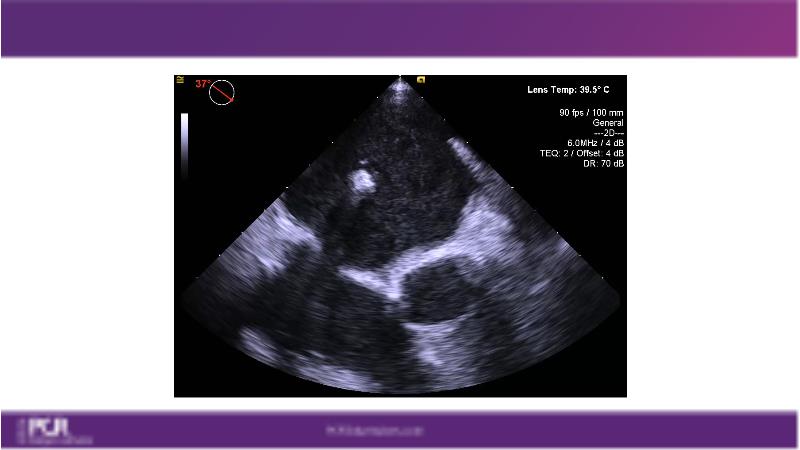

Watch this session to get an overview of a new TEER device, follow the step-by-step procedure related to initial experiences with this device for a Japanese patient with degenerative mitral regurgitation, learn about the latest data from RCT and registries, and follow discussions of challenging TEER cases!

- To learn procedural step-by-step of novel device